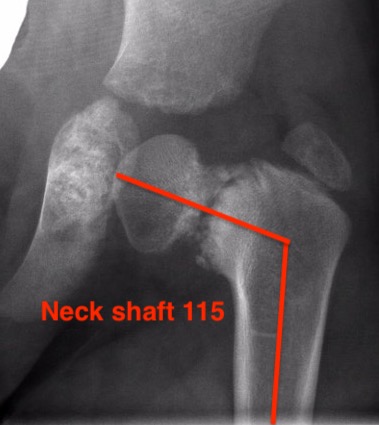

Deformity of proximal femur with neck-shaft angle <110°

Xray

| Varus femoral neck | Inverted Y | Hilgenreiner's epiphyseal angle |

Neck-shaft angle < 125°

Normal is 150° in infant |

Angle between Hilgenreiner's & physeal line

Normal < 25°

|

Management

Management based on Epiphyseal Angle

| < 45 degrees | 45 - 60 degrees | > 60 degrees |

Unlikely to progress

Observe | Surgery |

Observe

Surgery if progresses |